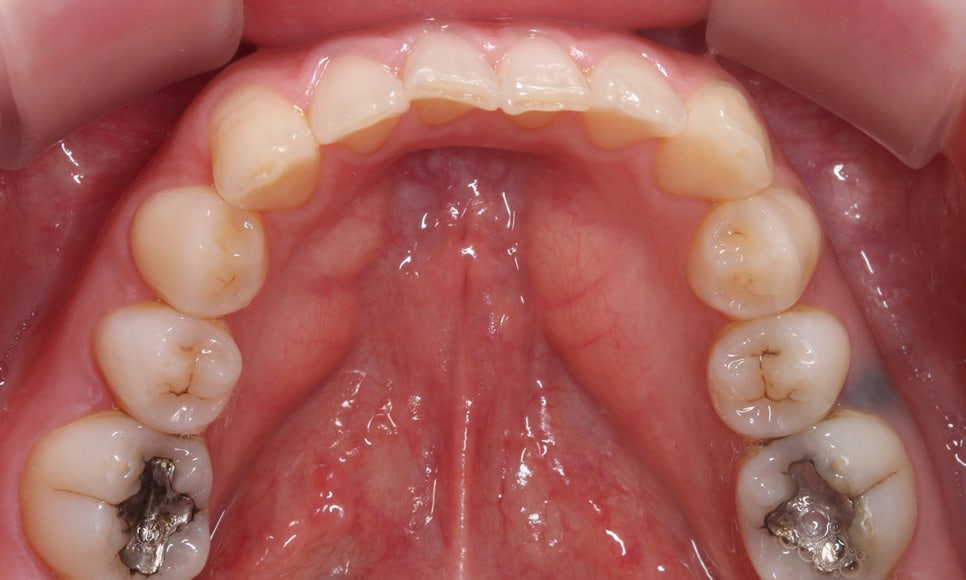

상악의 치아 배열을 보시면 우측 측절치가

설측으로 틀어져 있는 모습인데요,

안쪽으로 뻐드러진 측절치를 정상각도로

교정하고 튀어나온 송곳니를 덧니교정하여

상악의 치열을 바로잡기로 하였습니다.

하악의 경우 전치부에서 약간의

Crowding이 발견되는 모습입니다.